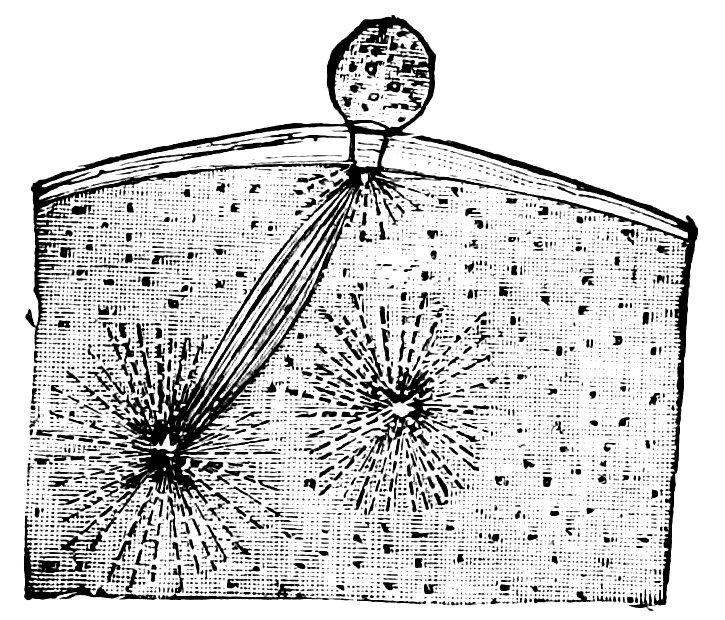

| 55. | First Stage. A. Entrance of a Spermatozoon into the Ovum of Ascaris Megalocephala. B. After preparations by M. Nussbaum. (Half of the ova only are depicted) | 306 |

| 56. | Ovum of Asterakanthion ten minutes after Fertilization | 306 |

| 57. | Fusion of Male Pro-nucleus and Female Pro-nucleus to form the Segmentation Nucleus of the Fertilized Ovum | 306 |

| 58. | Passage of Spermatozoon through the Zona Pellucida of the Ovum of Asterakanthion | 307 |

| 59. | Ovum of Scorpæna Scrofa Thirty-five Minutes after Fertilization | 307 |

| 60. | Male Pro-nucleus and Female Pro-nucleus in Fertilized Ovum of Frog, prior to the Formation of the Segmentation Nucleus | 307 |